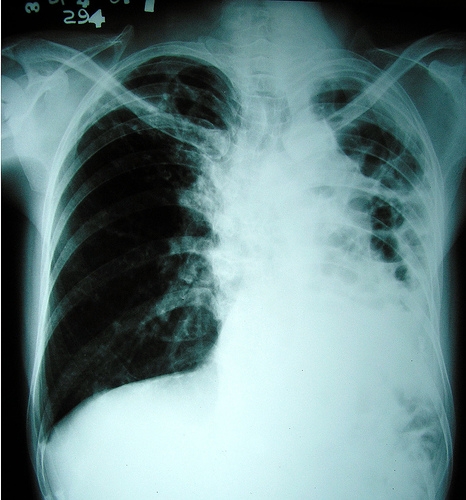

Pe 24 martie, este Ziua Mondială de Luptă Împotriva Tuberculozei, prilej cu care autorităţile publice din sănătate ne atrag atenţia asupra faptului că aceasta boală continuă să reprezinte o ameninţare serioasă. În cursul anului trecut, 517 gălăţeni au fost diagnosticaţi cu tuberculoză, dintre care 32 de copii cu vârste sub 14 ani. Galaţiul s-a situat, în 2011, pe locul V în ţară în funcţie de numărul de bolnavi de TBC. La momentul respectiv, coordonatorul tehnic al Programului Naţional de Control al TBC, dr. Marilena Tănase, ne informa că anul 128 de gălăţeni din 100.000 se prezintă la medic suferinzi de tuberculoză. Din nefericire, printre bolnavii gălăţeni se numără şi 29 de pacienţi în cazul cărora tuberculoza a dezvoltat o rezistenţă severă la medicamente. Astfel ca cazuri sunt destul de rare, anul trecut fiind înregistraţi circa 30.000 de pacienţi în întreaga lume.